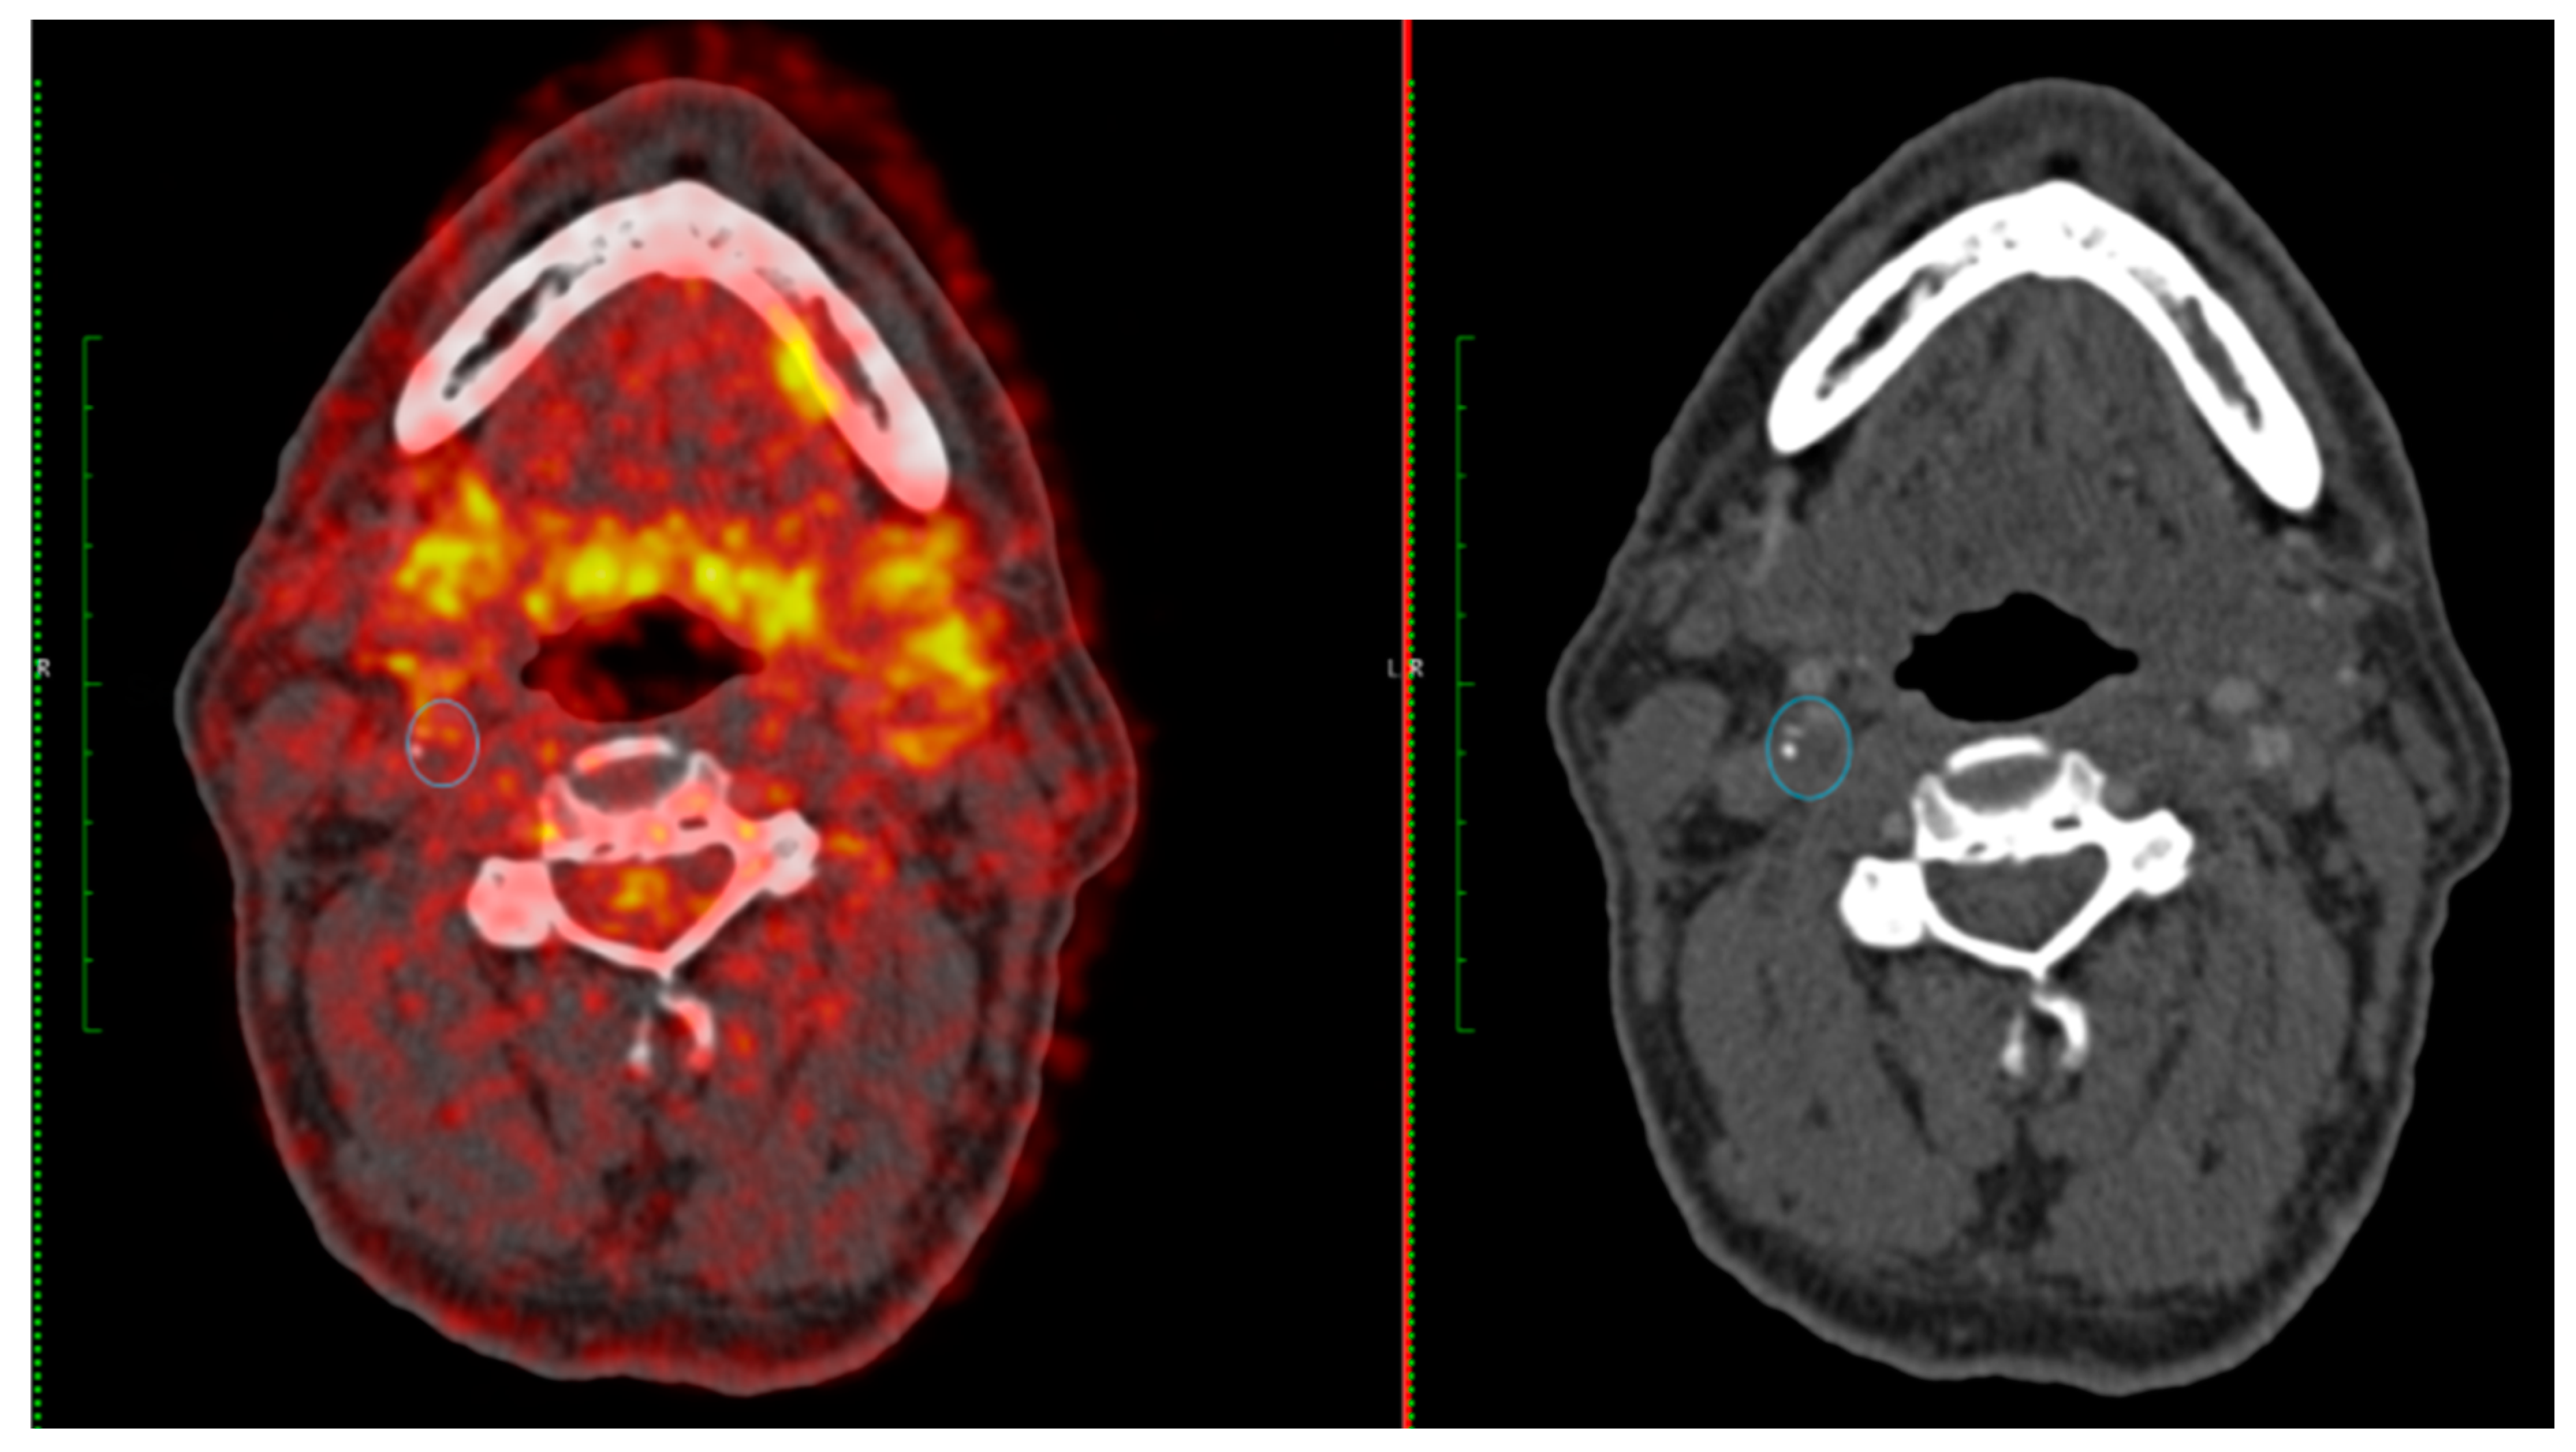

- Chaker S, Al-Dasuqi K, Baradaran H, et al. Carotid Plaque Positron Emission Tomography Imaging and Cerebral Ischemic Disease. Stroke 2019, 50, 2072–9. [Google Scholar] [CrossRef] [PubMed]

- Hyafil F, Schindler A, Sepp D, et al. High-risk plaque features can be detected in non-stenotic carotid plaques of patients with ischaemic stroke classified as cryptogenic using combined (18)F-FDG PET/MR imaging. Eur J Nucl Med Mol Imaging 2016, 43, 270–9. [Google Scholar] [CrossRef]

- Giannotti N, McNulty J, Foley S, et al. Association Between 18-FDG Positron Emission Tomography and MRI Biomarkers of Plaque Vulnerability in Patients With Symptomatic Carotid Stenosis. Frontiers in Neurology 2021, 12. [Google Scholar] [CrossRef]

- Moustafa RR, Izquierdo-Garcia D, Fryer TD, et al. Carotid plaque inflammation is associated with cerebral microembolism in patients with recent transient ischemic attack or stroke: a pilot study. Circulation Cardiovascular imaging 2010, 3, 536–41. [Google Scholar] [CrossRef]

- Muller HF, Viaccoz A, Fisch L, et al. 18FDG-PET-CT: an imaging biomarker of high-risk carotid plaques. Correlation to symptoms and microembolic signals. Stroke 2014, 45, 3561–6. [Google Scholar] [CrossRef] [PubMed]